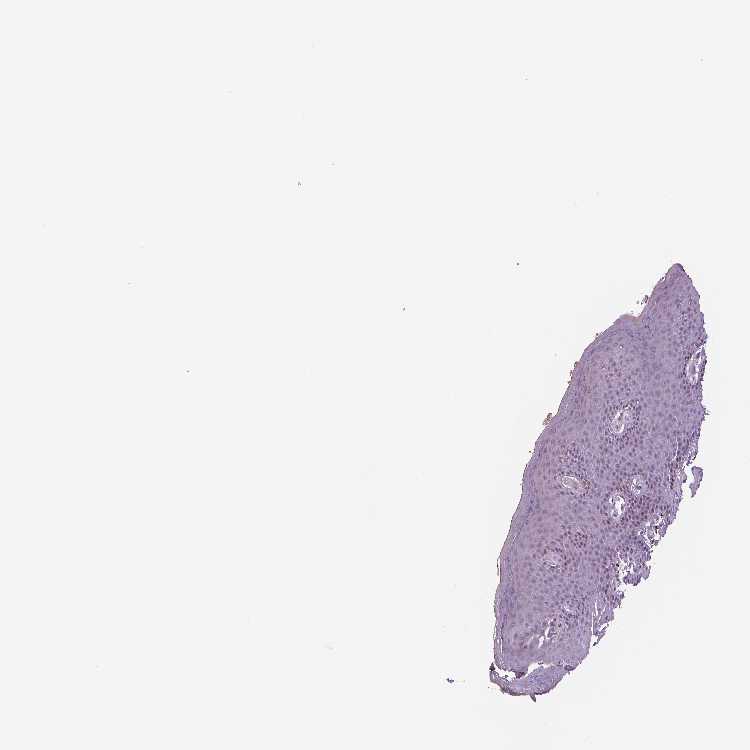

TISSUE PRIMARY DATA SKIN 1 Show tissue menu

Skin

SKIN - Expression summary

Protein expression

Skini

On the top, protein expression in current human tissue, based on all annotated cell types, is reported with the units not detected (n), low (l), medium (m) and high (h). Underneath, protein expression in each annotated cell type are reported using the same units.

Protein expression data is based on knowledge-based annotation. For genes where more than one antibody has been used, a collective score is set.

If knowledge-based annotation could not be performed for a gene, no data is displayed here. View antibody staining data further down this page.